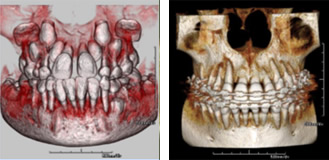

歯周病で歯を支える骨がどれくらいになっているか?

あるいは治療によりどれくらい骨が再生しているか?を立体画像で視覚的に見ることができますのでご自身の状態をおわかり頂けます。

インプラント治療において、あごの骨に埋めるインプラントを立体的にとらえて治療計画を立てられます。

インプラントの数、長さ、太さをあらゆる方向から診断して正確に決定することができ、神経などを避けて安全な位置、方向、埋める深さを、より確実に知ることも可能ですのでより確実な手術ができます。